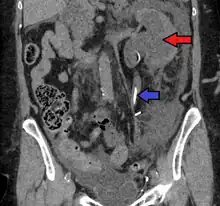

- Stone causing hydronephrosis[14]